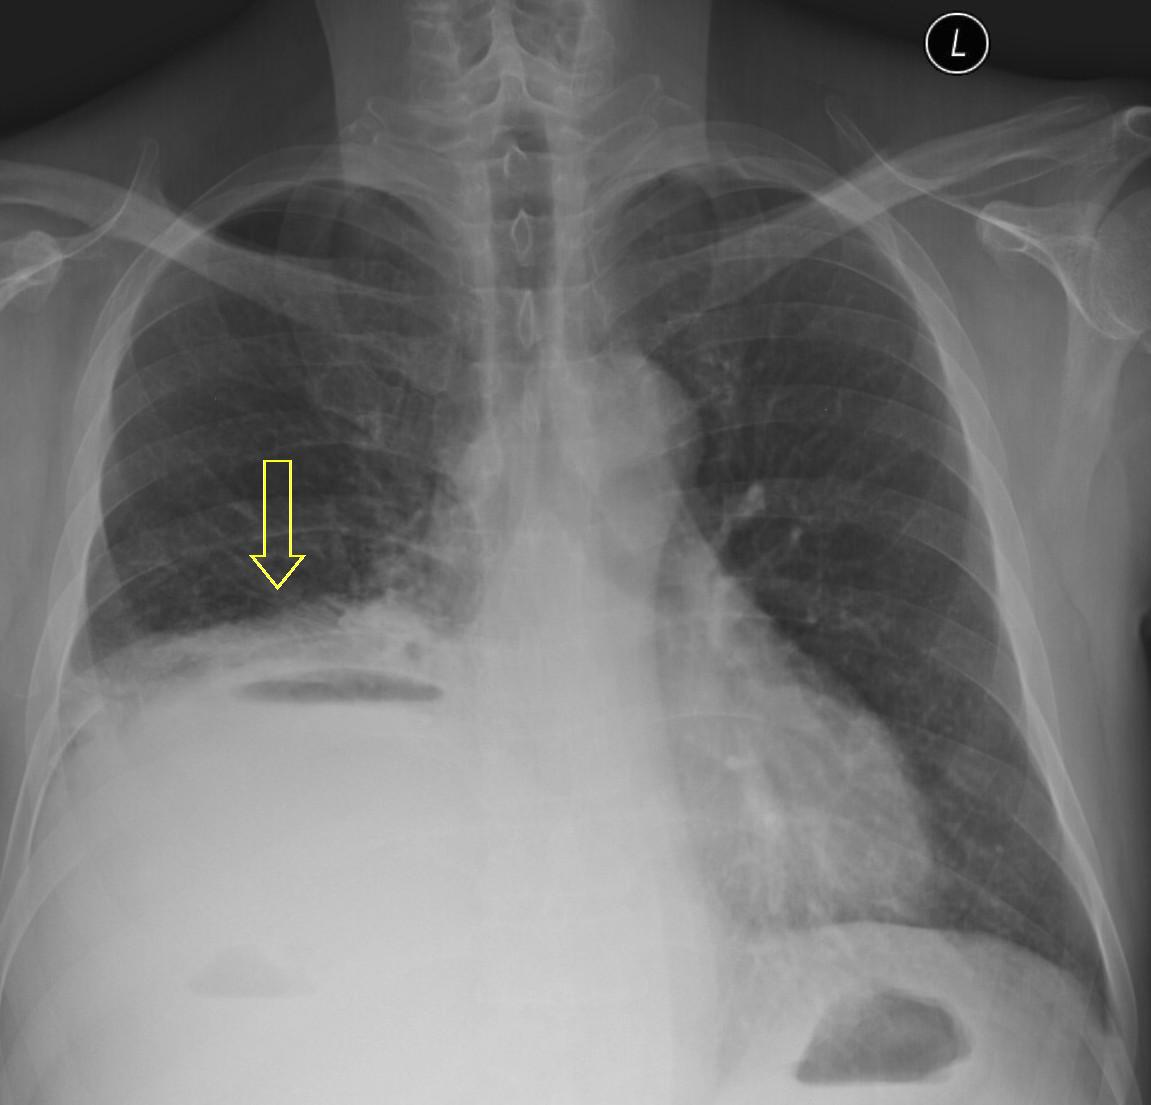

16. Right lobar pneumonia. a.) PA b.) lateral radiograph.

Mycoses